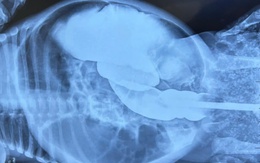

Bé gái 2 tháng tuổi mắc bệnh teo đại tràng bẩm sinh hiếm gặp

Một bé gái 2 tháng tuổi, bụng thường bị căng trướng, không đi tiêu nhiều ngày, nôn ói. Các bác sĩ Bệnh viện Nhi đồng Cần Thơ thăm khám phát hiện bé bị teo đại tràng bẩm sinh hiếm gặp.